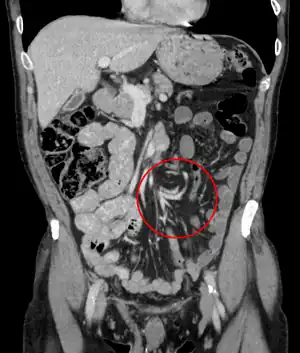

| Coronal CT of the abdomen, demonstrating a volvulus as indicated by twisting of the bowel stock | |

Coronal view of sigmoid volvulus with "whirlpool sign"